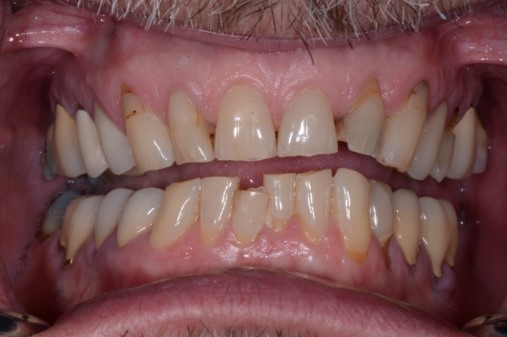

Tooth wear

Like pain, tooth wear can be multifactorial, but after a thorough history and clinical exam, we should be able to sort out tooth wear caused by extrinsic forces (acid erosion) vs. tooth wear caused by tooth-to-tooth contact (attrition).

Cases of attrition are often present in the unbalanced environment where a patient is naturally balancing themselves. The question here: What is the long-term consequence? Clinically, this can show anywhere from one canine with a flat incisal edge to an entire arch of teeth with completely flattened cusp tips. The worn area of one tooth or arch will have an equal and opposite pattern of wear in the other tooth or arch.